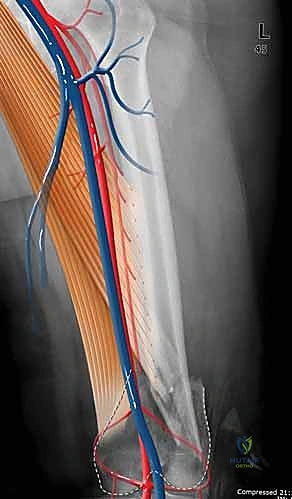

لفهم مدى تعقيد هذه الكسور، يجب أن نغوص في التشريح الدقيق لهذه المنطقة. يمثل الجزء السفلي من عظم الفخذ نقطة الارتكاز الأساسية لوزن الجسم أثناء الحركة والوقوف.

يمر المحور الميكانيكي لعظم الفخذ من مركز رأس عظم الفخذ إلى مركز الركبة، وعادة ما ينحرف بمقدار 3 درجات عن الخط العمودي. يستمر هذا المحور بعد ذلك إلى مركز الكاحل، ليحدد المحور الميكانيكي للطرف بأكمله. في المقابل، يظهر المحور التشريحي لعظم الفخذ مع حوالي 9 درجات من الانحراف الخارجي (Valgus) بالنسبة لمحور مفصل الركبة.

- التقييم السريري المبدئي: فحص النبض والأعصاب للتأكد من عدم وجود إصابات وعائية أو عصبية مصاحبة.

- الأشعة السينية (X-Rays): أخذ صور من زوايا متعددة (أمامي خلفي، وجانبي) لتحديد موقع الكسر ونوعه.

يستخدم الدكتور هطيف تقنيات الفتح الجراحي المحدود (Minimally Invasive Plate Osteosynthesis - MIPO) كلما أمكن ذلك، للحفاظ على التروية الدموية للعظم وتسريع الالتئام. يتم عمل شق جانبي بعناية للوصول إلى منطقة الكسر دون الإضرار بالعضلات المحيطة.

- الجراحة الميكروسكوبية: للتعامل مع الأعصاب والأوعية الدموية الدقيقة المحيطة بالركبة.